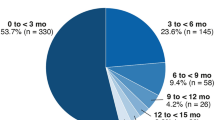

Subretinal fibrosis is the most common natural sequela of MNV and causes damage to the photoreceptors, RPE, and choriocapillaris, resulting in irreversible loss of central vision (Bressler 1988; Wong et al. 2008). Cheung et al. reported an increase of subretinal fibrosis in patients with treatment-naive nAMD from 13.0 to 37.8% within 1 year (Cheung et al. 2019). Histopathological studies show that the severity of photoreceptor damage is proportional to the size of subretinal fibrosis in AMD eyes (Green and Enger 1993), supporting the clinical observation that subretinal fibrosis is the most important predictor of final visual acuity (Cheung et al. 2019). The risk of eyes with nAMD to develop subretinal fibrosis despite ongoing anti-VEGF therapy is reported to be 45% by 2 years (Daniel et al. 2014) and 41% by 10 years (Teo et al. 2020). This is of particular concern because eyes with subfoveal fibrotic scarring after anti-VEGF treatment have the worst prognosis in terms of visual acuity after anti-VEGF treatment (Daniel et al. 2014). Therefore, alternative therapeutic strategies are needed to circumvent the dilemma of inhibiting vessel growth but risking the promotion of scar formation at the same time. Clinically, subretinal fibrosis can be evaluated by funduscopy, fluorescein angiography, and polarization-sensitive optical coherence tomography (PS-OCT) and categorized into fibrotic and non-fibrotic scars (Roberts et al. 2019). While fibrotic scars are characterized as raised clusters of white or yellowish tissue that are well-defined in shape and appear solid on funduscopy, non-fibrotic scars are typically flat, unpigmented lesions with varying amounts of peripheral dark pigmentation. Fibrotic and non-fibrotic scars can both develop with ongoing anti-VEGF therapy, occurring in 24.7% and 20.6% of cases with nAMD after 2 years of therapy, respectively (Daniel et al. 2014). However, it is unclear whether these clinical subtypes of subretinal fibrosis represent pathophysiologically distinct entities or converging disease stages.